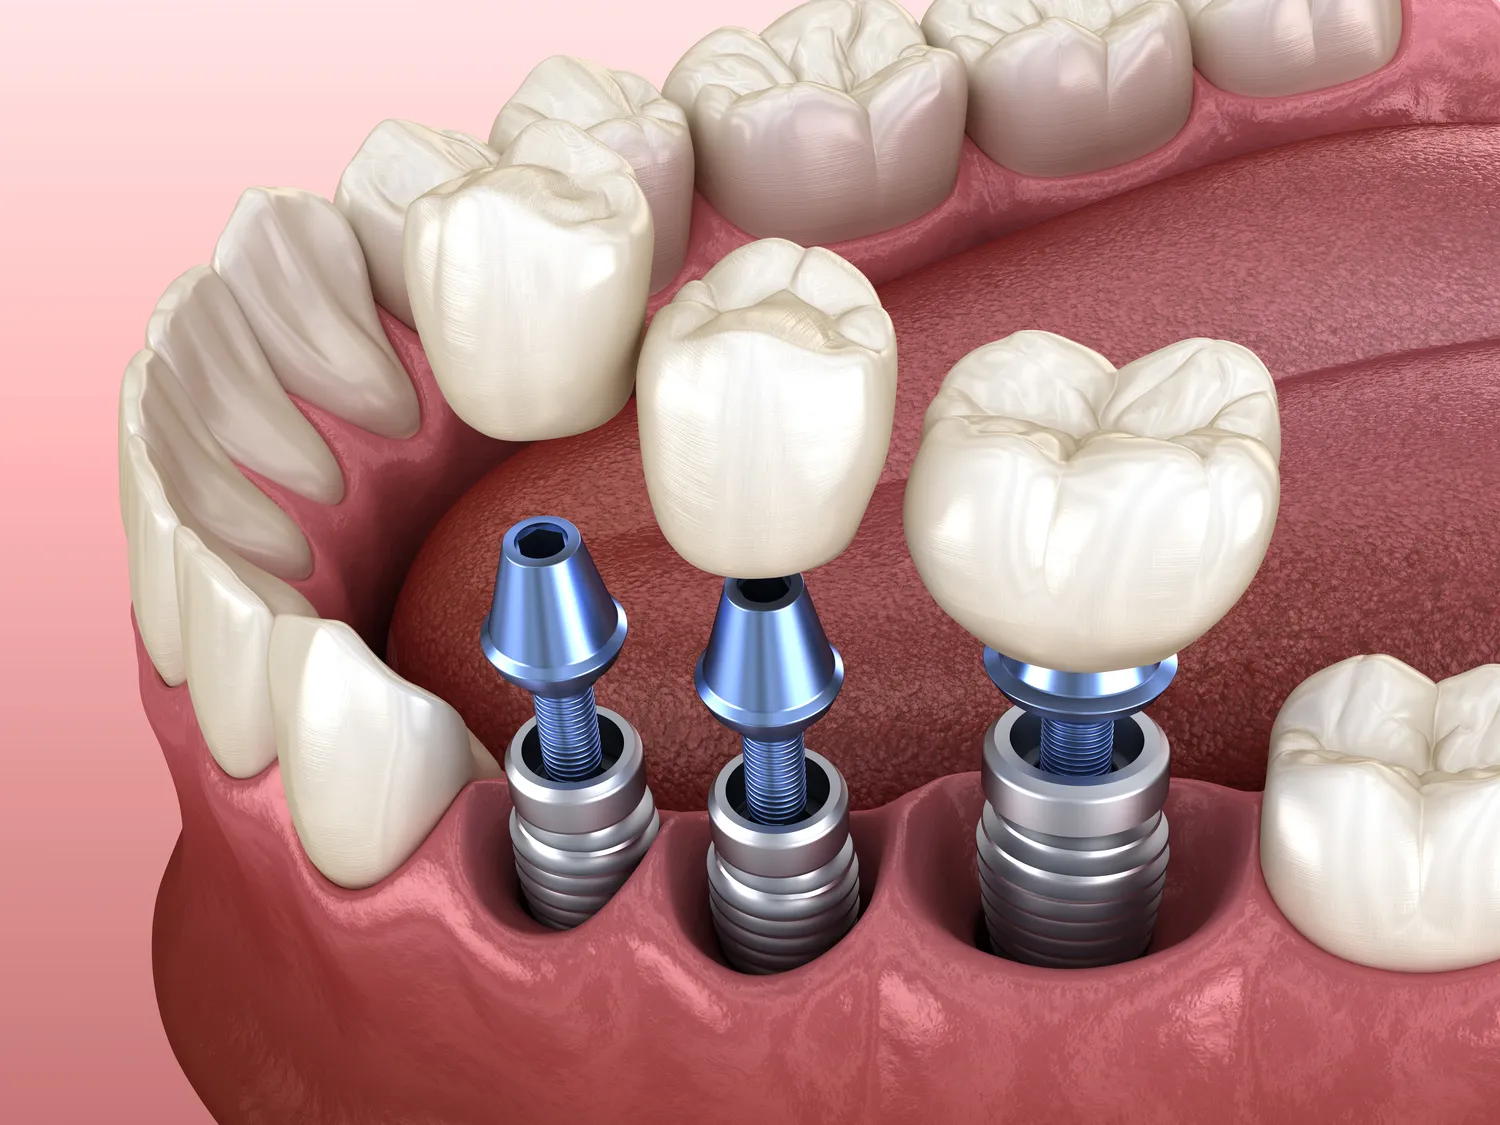

Proces wszczepiania implantów zębowych składa się z kilku etapów, które wymagają staranności oraz precyzji ze strony lekarza stomatologa. Pierwszym krokiem jest dokładna diagnostyka, która obejmuje badania radiologiczne oraz ocenę stanu zdrowia pacjenta. Na podstawie tych informacji lekarz podejmuje decyzję o rodzaju implantu oraz planuje zabieg. Kolejnym etapem jest chirurgiczne wszczepienie implantu do kości szczęki lub żuchwy. Zabieg ten zazwyczaj przeprowadza się w znieczuleniu miejscowym, co minimalizuje dyskomfort pacjenta. Po wszczepieniu implantu następuje okres gojenia, który trwa od kilku tygodni do kilku miesięcy. W tym czasie implant integruje się z kością, co jest kluczowe dla jego stabilności i funkcjonalności. Po zakończeniu procesu gojenia można przystąpić do wykonania korony protetycznej, która będzie pełniła funkcję estetyczną oraz funkcjonalną.